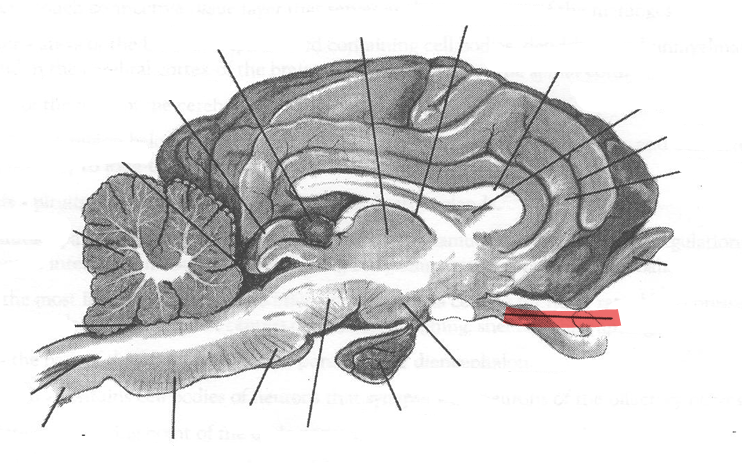

Identify highlighted arrow

Spinal cord

2

New cards

Identify highlighted arrow

Medulla

3

New cards

Identify highlighted arrow

Pons

4

New cards

Identify highlighted arrow

Midbrain

5

New cards

Identify highlighted arrow

Hypophysis

6

New cards

Identify highlighted arrow

Hypothalamus

7

New cards

Identify highlighted arrow

Optic nerve

8

New cards

Identify highlighted arrow

Olfactory bulb

9

New cards

Identify highlighted arrow

Gyrus

10

New cards

Identify highlighted arrow

Sulcus

11

New cards

Identify highlighted arrow

Corpus callosum

12

New cards

Identify highlighted arrow

Third ventricle

13

New cards

Identify highlighted arrow

Thalamus

14

New cards

Identify highlighted arrow

Pineal body

15

New cards

Identify highlighted arrow

cerebellum

16

New cards

Identify highlighted arrow

Fourth ventricle